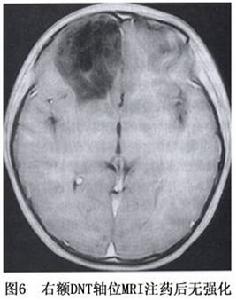

神經元腫瘤和神經元與神經膠質混合性腫瘤圖6

神經節膠質瘤在CT上表現呈多樣性,大多數為低密度或等密度,少數為高密度,腫瘤邊界清鈣化或囊變各約1/3半數注藥後可出現混雜性增強,腫瘤對腦組織占位效應不明顯水腫少見,但位於大腦皮質表面的腫瘤可使顱骨內板受壓而局部變薄。MRI檢查T1加權像為低信號、T2為高信號、邊界清晰的占位影,病灶周圍腦回可有腫脹(圖1)。鈣化發生率不到1/10。約10%在頭顱平片中可發現鈣化影。

小腦發育不良性神經節細胞瘤CT為低密度或低與等密度相交替的混雜密度可累及一側小腦半球,偶有鈣化,有輕度占位效應,可幕上腦室擴大及四腦室輕度移位。MRI可見小腦半球異常增大,腫瘤無明顯占位效應,T1像為沿小腦溝排列的低信號和等信號的分層結構T2像為高信號和等信號交錯形成“虎紋征”(圖2,3)。注藥無強化。